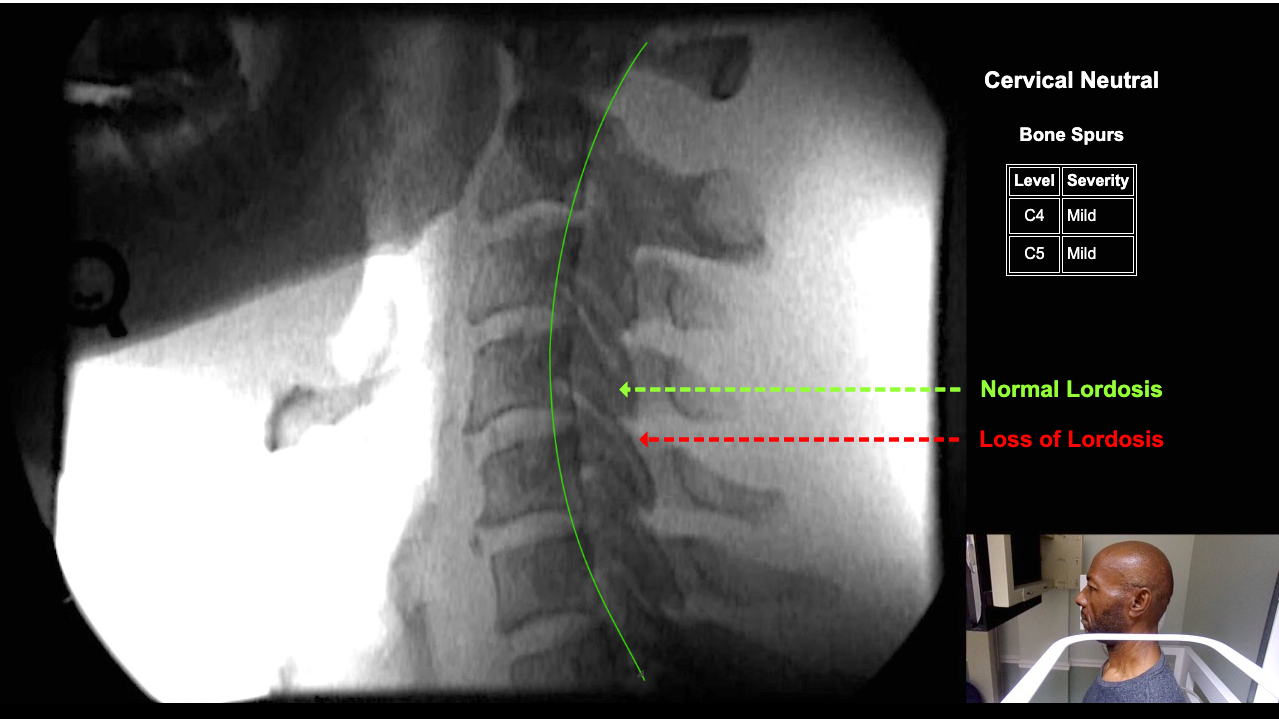

Image Name Image Type Image